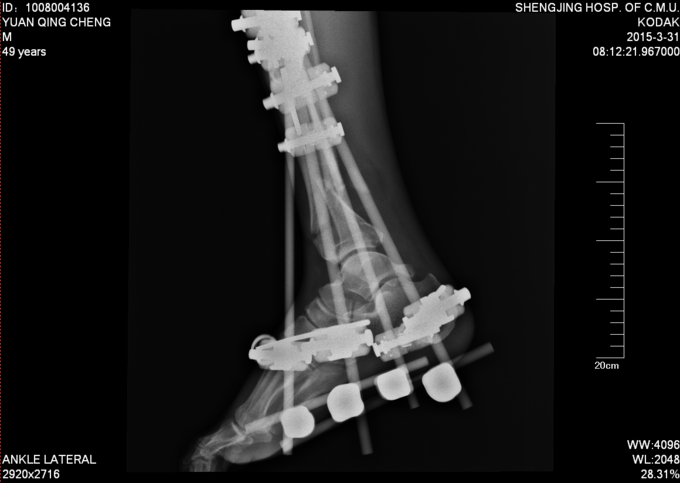

诊断:左胫腓骨远端开放性粉碎性骨折 患者车祸入院后行行抗炎消肿止疼等对症治疗后约一周,局部皮肤软组织条件差,局部皮肤全层坏死,行左胫腓骨远端外固定架固定术。

患者皮肤条件差,行外固定架维持患肢长度,如果直接行内固定治疗,切口处易感染,危险。